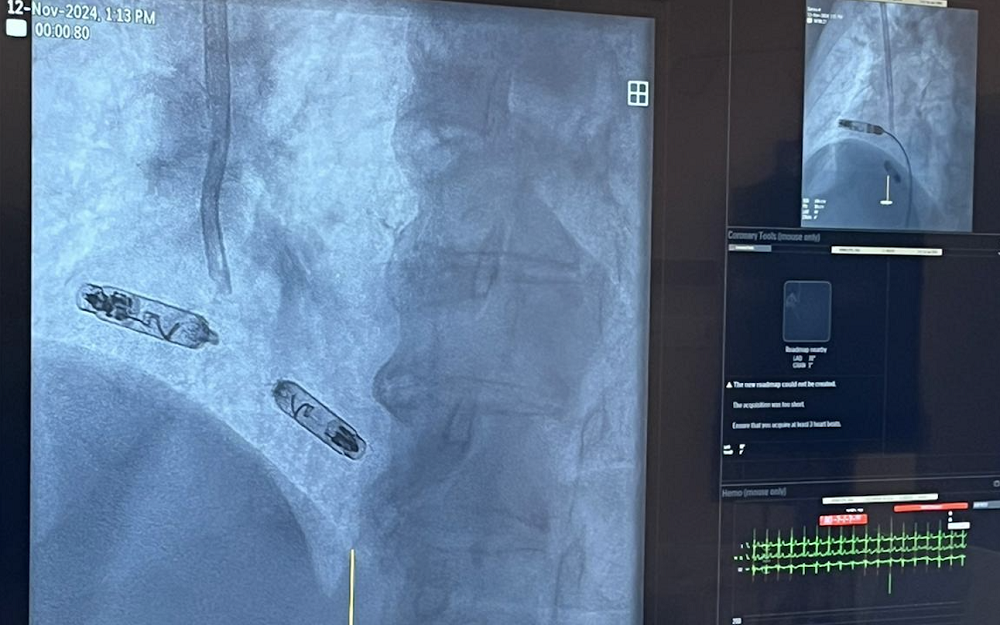

We wtorek 12 listopada 2024 roku odbyły się pierwsze na Śląsku zabiegi wszczepienia nowego bez elektrodowego dwujamowego stymulatora serca. Zabiegi z zastosowaniem nowej technologii odbyły się w III Katedrze i Klinice Kardiologii Śląskiego Centrum Chorób Serca w Zabrzu.

Zaimplantowany pacjentkom podczas wtorkowych zabiegów w Śląskim Centrum Chorób Serca innowacyjny system do elektroterapii kardiologicznej to pierwszy dwukomorowy bezelektrodowy stymulator serca.

– Nowy system do stymulacji bezelektrodowej to dwa stymulatory -„kapsułki” o wielkości mniejszej niż bateria AAA (to około jednej dziesiątej wielkości tradycyjnego stymulatora serca). Po zaimplantowaniu i aktywacji stymulatory-kapsułki komunikują się ze sobą niskonapięciowymi impulsami, dzięki czemu możliwa jest nie tylko stała stymulacja serca, ale także jednoczesna właściwa synchronizacja między pracą prawego przedsionka i prawej komory serca pacjenta. W nowym systemie możliwa jest także stymulacja DDD, „na żądanie” stymulacji przedsionków i na żądanie stymulacji komór. Te możliwości przekładają się na jeszcze skuteczniejszą terapię bradykardii i jeszcze lepszą jakość życia pacjenta po wdrożeniu terapii – tłumaczy dr hab. n. med. Mateusz Tajstra.